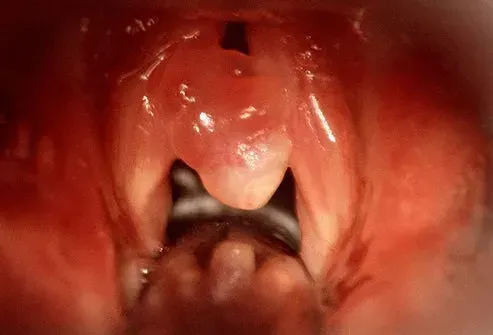

Polypper i halsen udvikler sig normalt på kun halvdelen af ​​dine V-formede stemmebånd. Deres former og størrelser varierer, og de forstyrrer lyden af ​​din stemme på mange måder. Din stemme lyder måske hes ridset åndedræt eller ru. Du kan også opleve smerteskydning fra øre til øre. Vokale polypper kan forårsage træthedhalsmerter og en følelse af, at du har en klump i halsen. Vokale polypper er ikke -kræft.

For at kontrollere for vokale polypper bruger en læge enten et spejl eller et synsrør kaldet et laryngoskop. Nogle gange skraber en læge din hals og sender resultaterne tilbage til test i en proces, der kaldes en biopsi.

En form for fjernelse af polypfjernelse kaldes phonomicrosurgery. For at udføre denne operation bruger kirurgen et slanke rør kaldet et endoskop sammen med et mikroskop for at fjerne væksten.